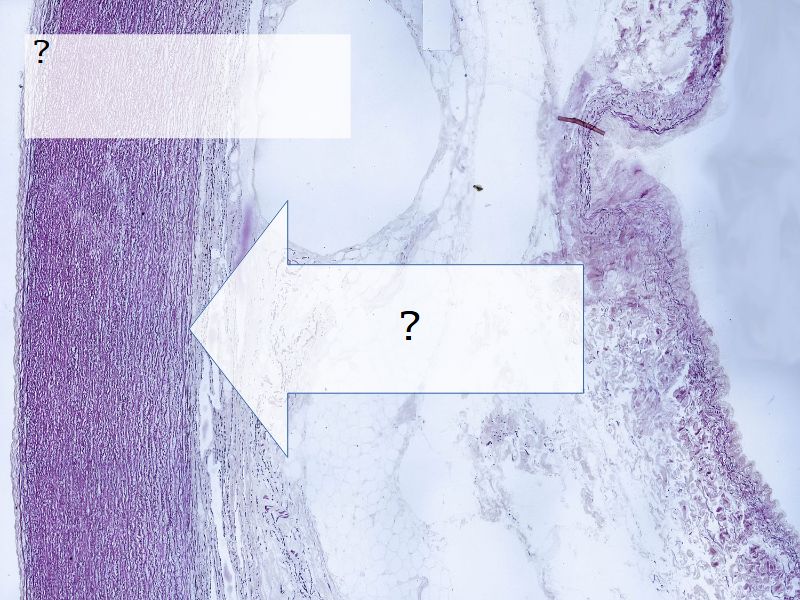

Fill in all the missing labels, and assess as you move through the slides. Answers on the down slide. It is important to do this using pen and paper, and not just glance through the images.